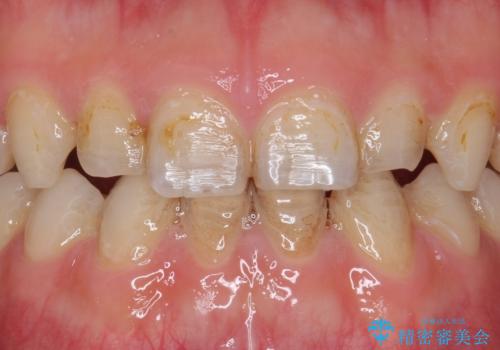

- K-POP(Kポップ)アイドルのような歯にしたいと希望され来院された患者様です。

矯正を途中でやめてしまったとのことで、歯に矯正の接着材が残っており着色も顕著でした。

奥歯の咬合面にはレジンが盛られた状態でした。

見た目と咬み合わせを改善するため、セラミッククラウンによる治療を行いました。